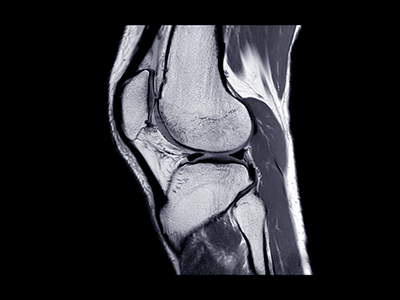

Objetivo: comparar la técnica anteromedial versus la técnica transtibial para la realización del túnel femoral en la reconstrucción del ligamento cruzado anterior, con el fin de valorar si hay diferencias clínicas.

Métodos: revisión sistemática de ensayos clínicos aleatorizados que comparen los resultados clínicos de la técnica anteromedial versus la técnica transtibial en la reconstrucción del ligamento cruzado anterior. Se analizaron las variables demográficas, clínicas y quirúrgicas, incluyendo tipo de injerto, escalas funcionales y complicaciones.

Resultados: 9 ensayos clínicos aleatorizados fueron seleccionados. Se analizaron 763 pacientes: 386 pacientes (50,6%) operados mediante la técnica anteromedial y 377 pacientes (49,4%) operados mediante la técnica transtibial. Los resultados posquirúrgicos agrupados no encontraron diferencias significativas entre ambas técnicas en cuanto a la puntuación de Lysholm (p = 0,06), ni a la escala del International Knee Documentation Committee (IKDC) (p = 0,23), ni a la puntuación de Tegner (p = 0,97). Tampoco se encontraron diferencias en el número de complicaciones postoperatorias (p = 0,42), ni en el número de reintervenciones (p = 0,93).

Conclusiones: la técnica anteromedial y la transtibial en la reconstrucción del ligamento cruzado anterior tienen resultados